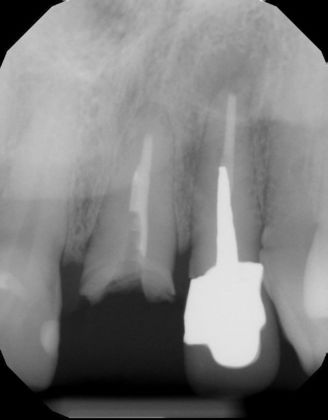

Dental Implants: Case 43

Upper front central incisor fractured and was replaced by an implant crown